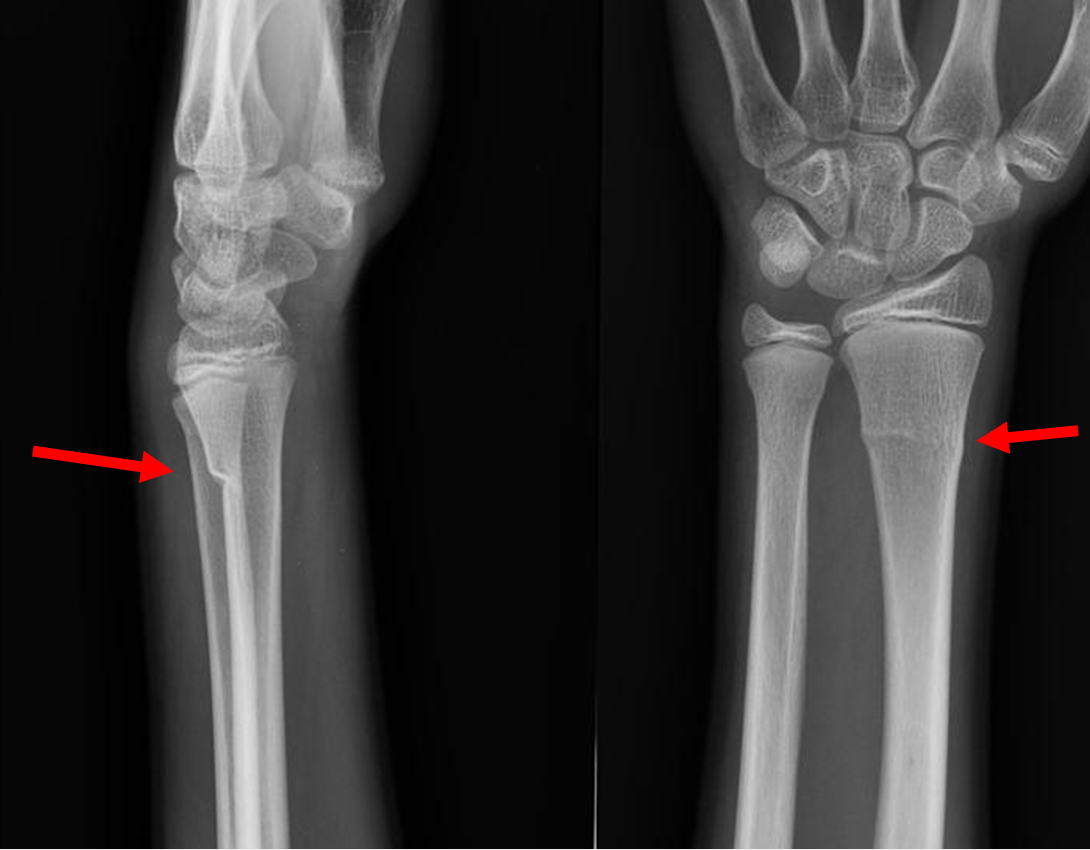

Example xray of greenstick fracture of distal radius:

(demonstrating extension of fracture line to volar cortex with angulation of the volar cortex)

Images from:

Royal Children's Hospital Melbourne - Greenstick fracture distal radius